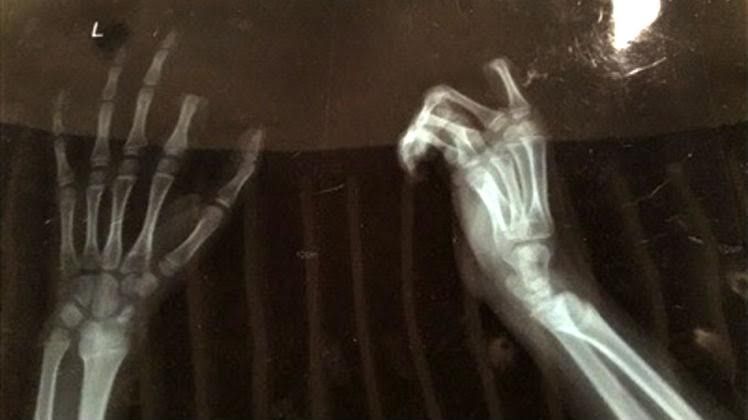

Në Suzhou të Kinës, një fëmijë e ka prerë gishtin tregues pasi është kritikuar nga babai se po humb shumë kohë në telefonin e zgjuar.

Djaloshi 11-vjeçar e ka marrë thikën dhe e ka prerë gishtin, kur i është kërkuar të lë pajisjen dhe t’i ndihmojë vëllait për të kryer detyrat e shtëpisë, transmeton Telegrafi.

Atë e kanë dërguar shpejtë në spital, ku i është nënshtruar intervenimit prej tri orësh, për t’i ngjitur gishtin.

Mirëpo, mjekët kanë thënë se vetëm pas një jave do të kuptojnë nëse intervenimi do të ketë sukses. /Telegrafi/